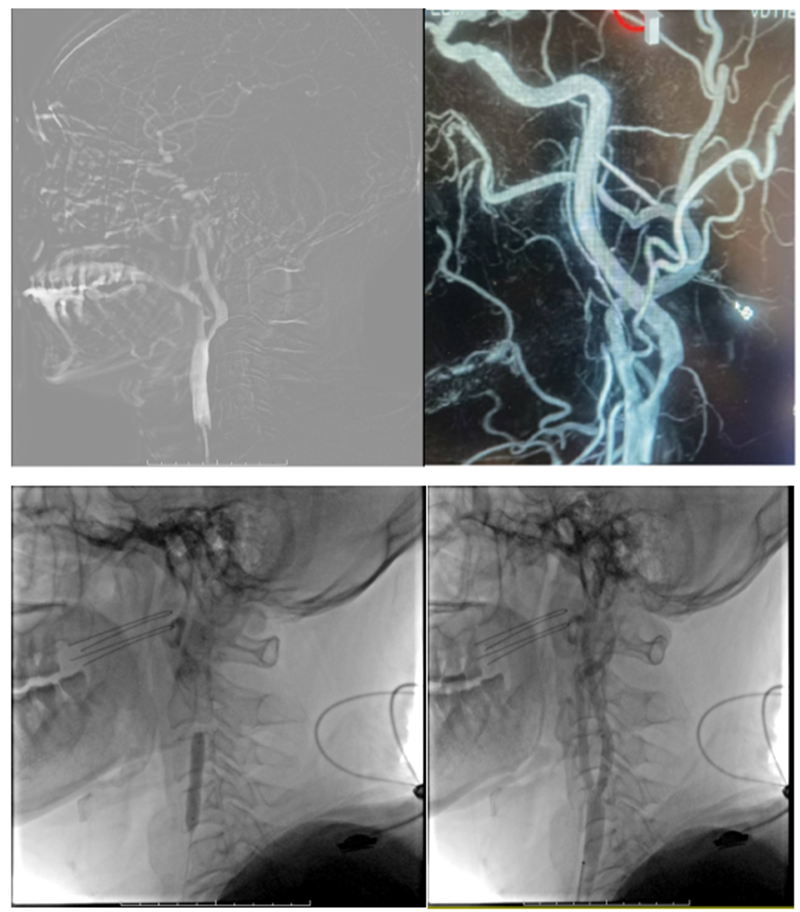

在经过沟通并征得患者家属同意后收住入院,由外二科王贤光副主任医师、吴海浪主治医师对患者进行详细的术前评估及相关术前准备后,决定为其进行全脑血管造影+脑保护伞下右侧颈内动脉狭窄球囊扩张成形+支架置入术。手术在局麻下进行,术中脑血管造影进一步明确右侧颈内动脉起始部重度狭窄。首先为防止球囊扩张过程中栓子脱落向远端血管“逃逸”导致颅内血管栓塞,经血管内狭窄部位远端放置脑保护伞,球囊对狭窄段扩张后,置入支架,回收保护伞。术后即刻脑血管造影显示狭窄血管形态基本恢复正常状态。术后患者感头晕症状较前缓解,“告别”眩晕。如下是相关术中情况: